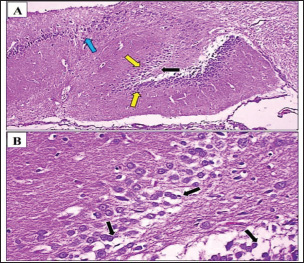

In contrast, the positive control group, which only received AlCl3 treatment, exhibited pronounced histopathological changes. There was a significant reduction in the number of granule cells compared to the negative control group (Fig. 2A,B), along with clear signs of neuronal loss and degeneration in the dentate gyrus of the hippocampus. This was evidenced by cytoplasmic vacuolization and gaps, indicating neuronal damage. Furthermore, a statistically significant (p < 0.05) increase in amyloid beta protein aggregation was observed in this group, as shown in Table 1.

Fig. 1. Photomicrograph of the hippocampus of rat treated with Arabic Gum. (A, B) Neurodegeneration (black arrow) was observed in the dentate gyrus stratum granulosum cells within the affected hippocampus, characterized by the presence of cytoplasmic vacuoles in granule cells. Additionally, the density of granule cells (yellow arrow) was lower in the negative control group than in the positive control group, likely due to neuronal loss in the dentate gyrus. However, the number of granule cells was higher in the positive control group than in the positive control group. In addition, mild neurodegeneration (blue arrow) was observed in neurocyte of Cornu Ammonis region 3. H&E. A: 100x and B: 400x.

The Gum Arabic-treated group demonstrated notable improvement relative to the positive control group. Histological analysis (Fig. 3A,B) revealed less severe neurodegeneration, with a higher number of granule cells, suggesting a partial neuroprotective effect. Amyloid beta accumulation was reduced by approximately 50% in the Cornu Ammonis region compared with that in the negative control group (Fig. 4). Statistical analysis confirmed a significant (p < 0.05) increase in cell preservation in the Gum Arabic group compared with the Fenchol and memantine groups. In the Fenchol-treated group, histological assessment showed reduced granule cell density compared with the negative control, but with minimal amyloid beta deposition, particularly in the hippocampus, where plaques were nearly absent (Fig. 5A,B). The histogram in Figure 6 demonstrated a statistically significant (p < 0.05) protective effect in this group compared with both the Gum Arabic and memantine groups.